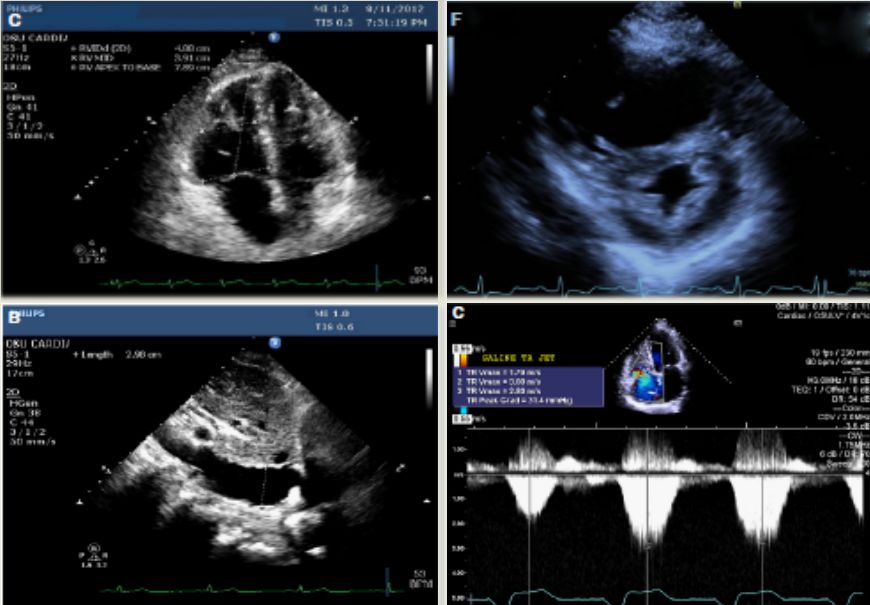

超声心动图

右心衰:右室大,左室小,左室呈D形,少量心包积液

Rudski LG, et al. J Am Soc Echocardiogr 2010;23:685–71